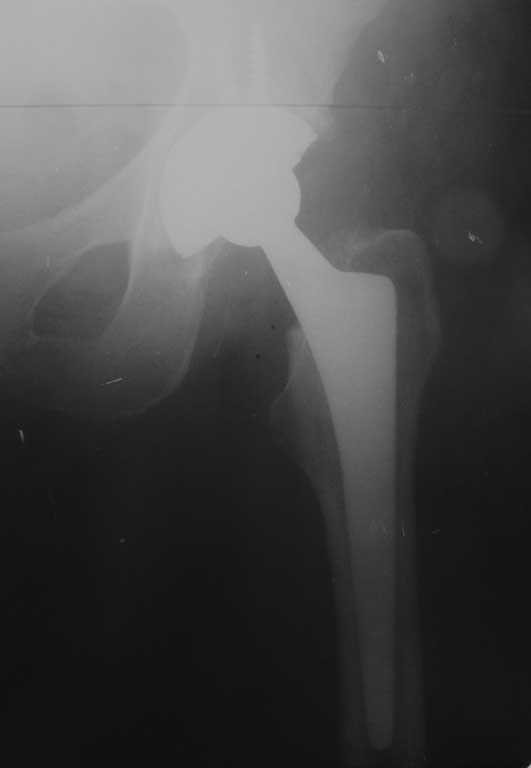

Уважаемые коллеги. Помогите определиться с тактикой лечения при перипротезном переломе

бедра. Женщина 58 лет, ранее (в марте 2010г.) оперирована в нашем отделении по поводу

перелома шейки бедра. Выполнено эндопротезирование сустава бесцементным протезом Зиммер

(чашка Трилоджи и ножка Споторно). До получения последней травмы пациентка чувствовала

себя хорошо: ходила не хромая , болей не было. 28.12.11 упала на улице. На рентгенограммах

имеется перипротезный перелом бедра в верхней трети, проседание ножки протеза. Помогите с

выбором тактики лечения. Наше мнение : ревизовать ножку на более длинную, предварительно

выполнить остеосинтез бедра серкляжами. Вот только какую ножку выбрать: цементную или

безцементную, Вагнера или Гелио (биомет) или длинную цементную ножку Экзетер(Страйкер).